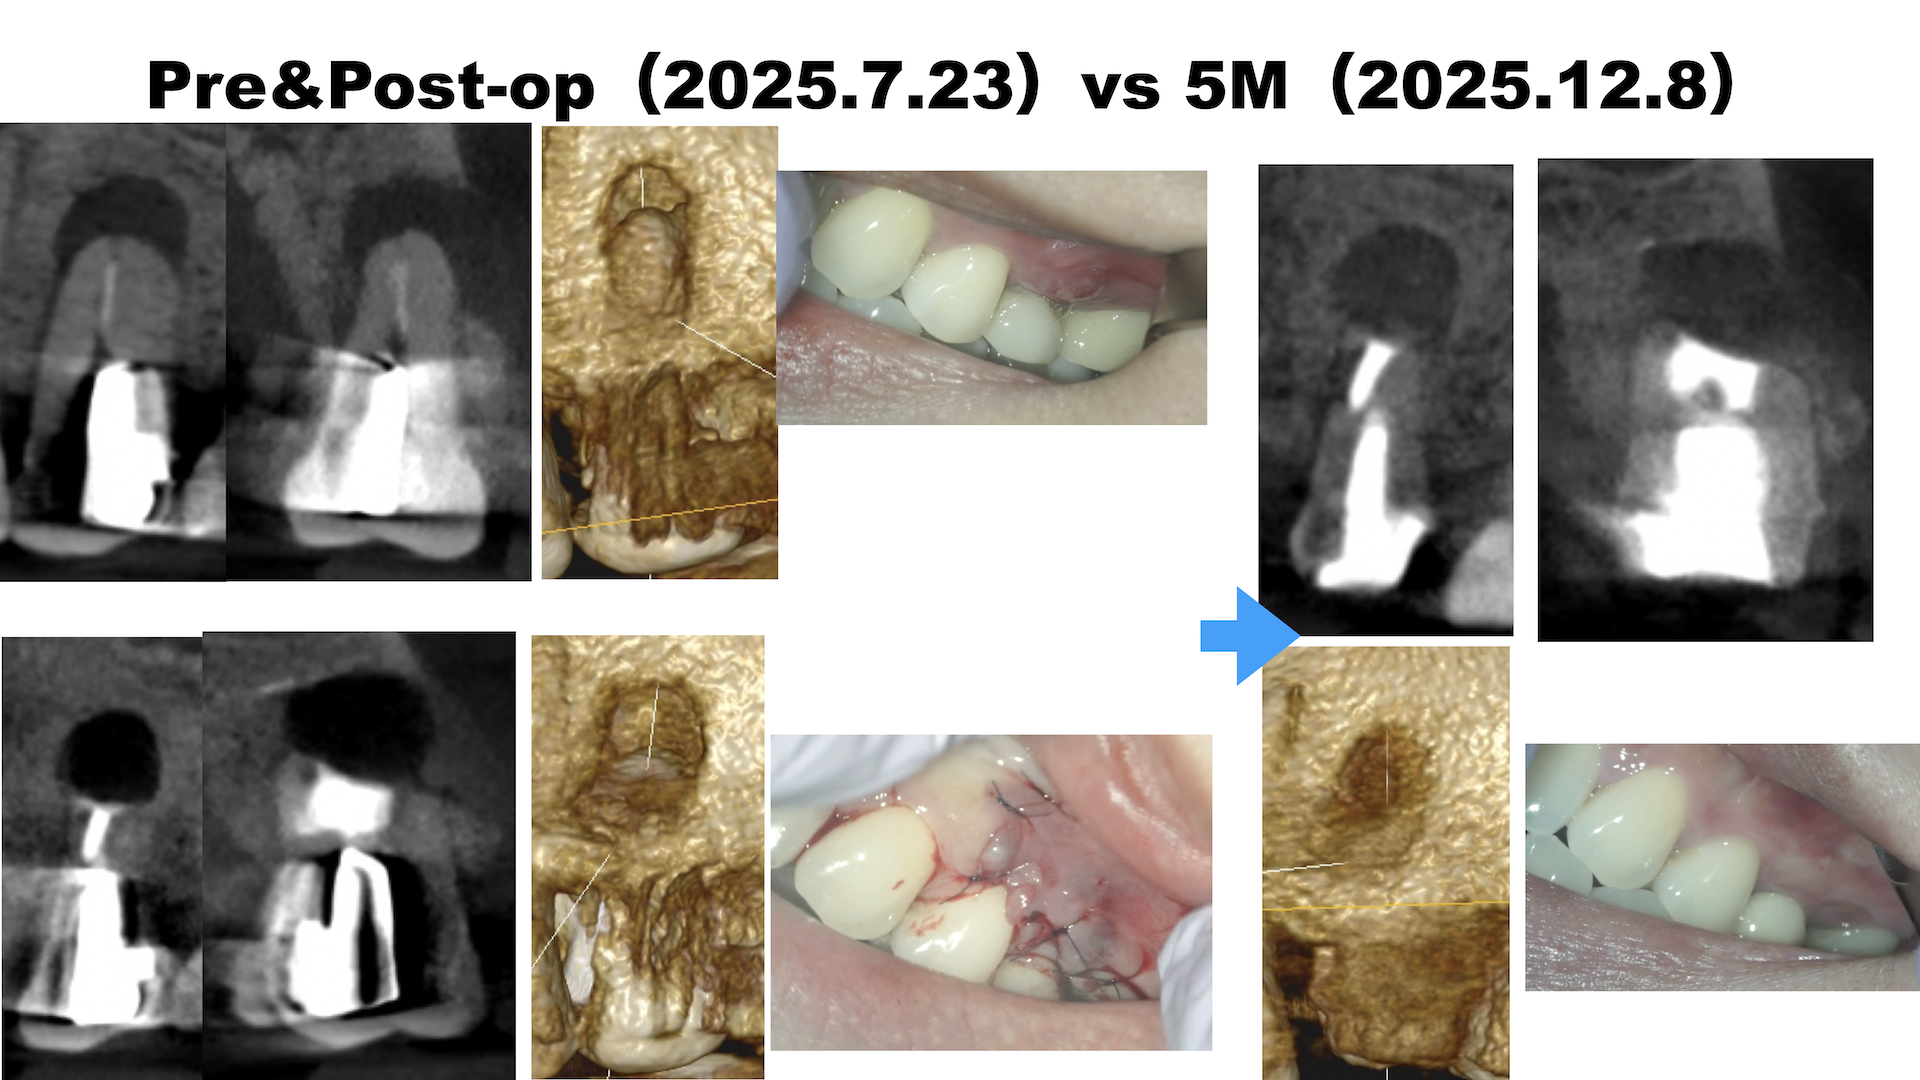

#13 Apicoectomy 5M recall(2025.12.8)

歯肉の腫脹は消失した。

劇的に歯槽骨が回復している。

そして歯肉はどうだろうか?

特に抜糸時は以下のような痛々しい状態だった。

治療前・直後と5ヶ月後を比較した。